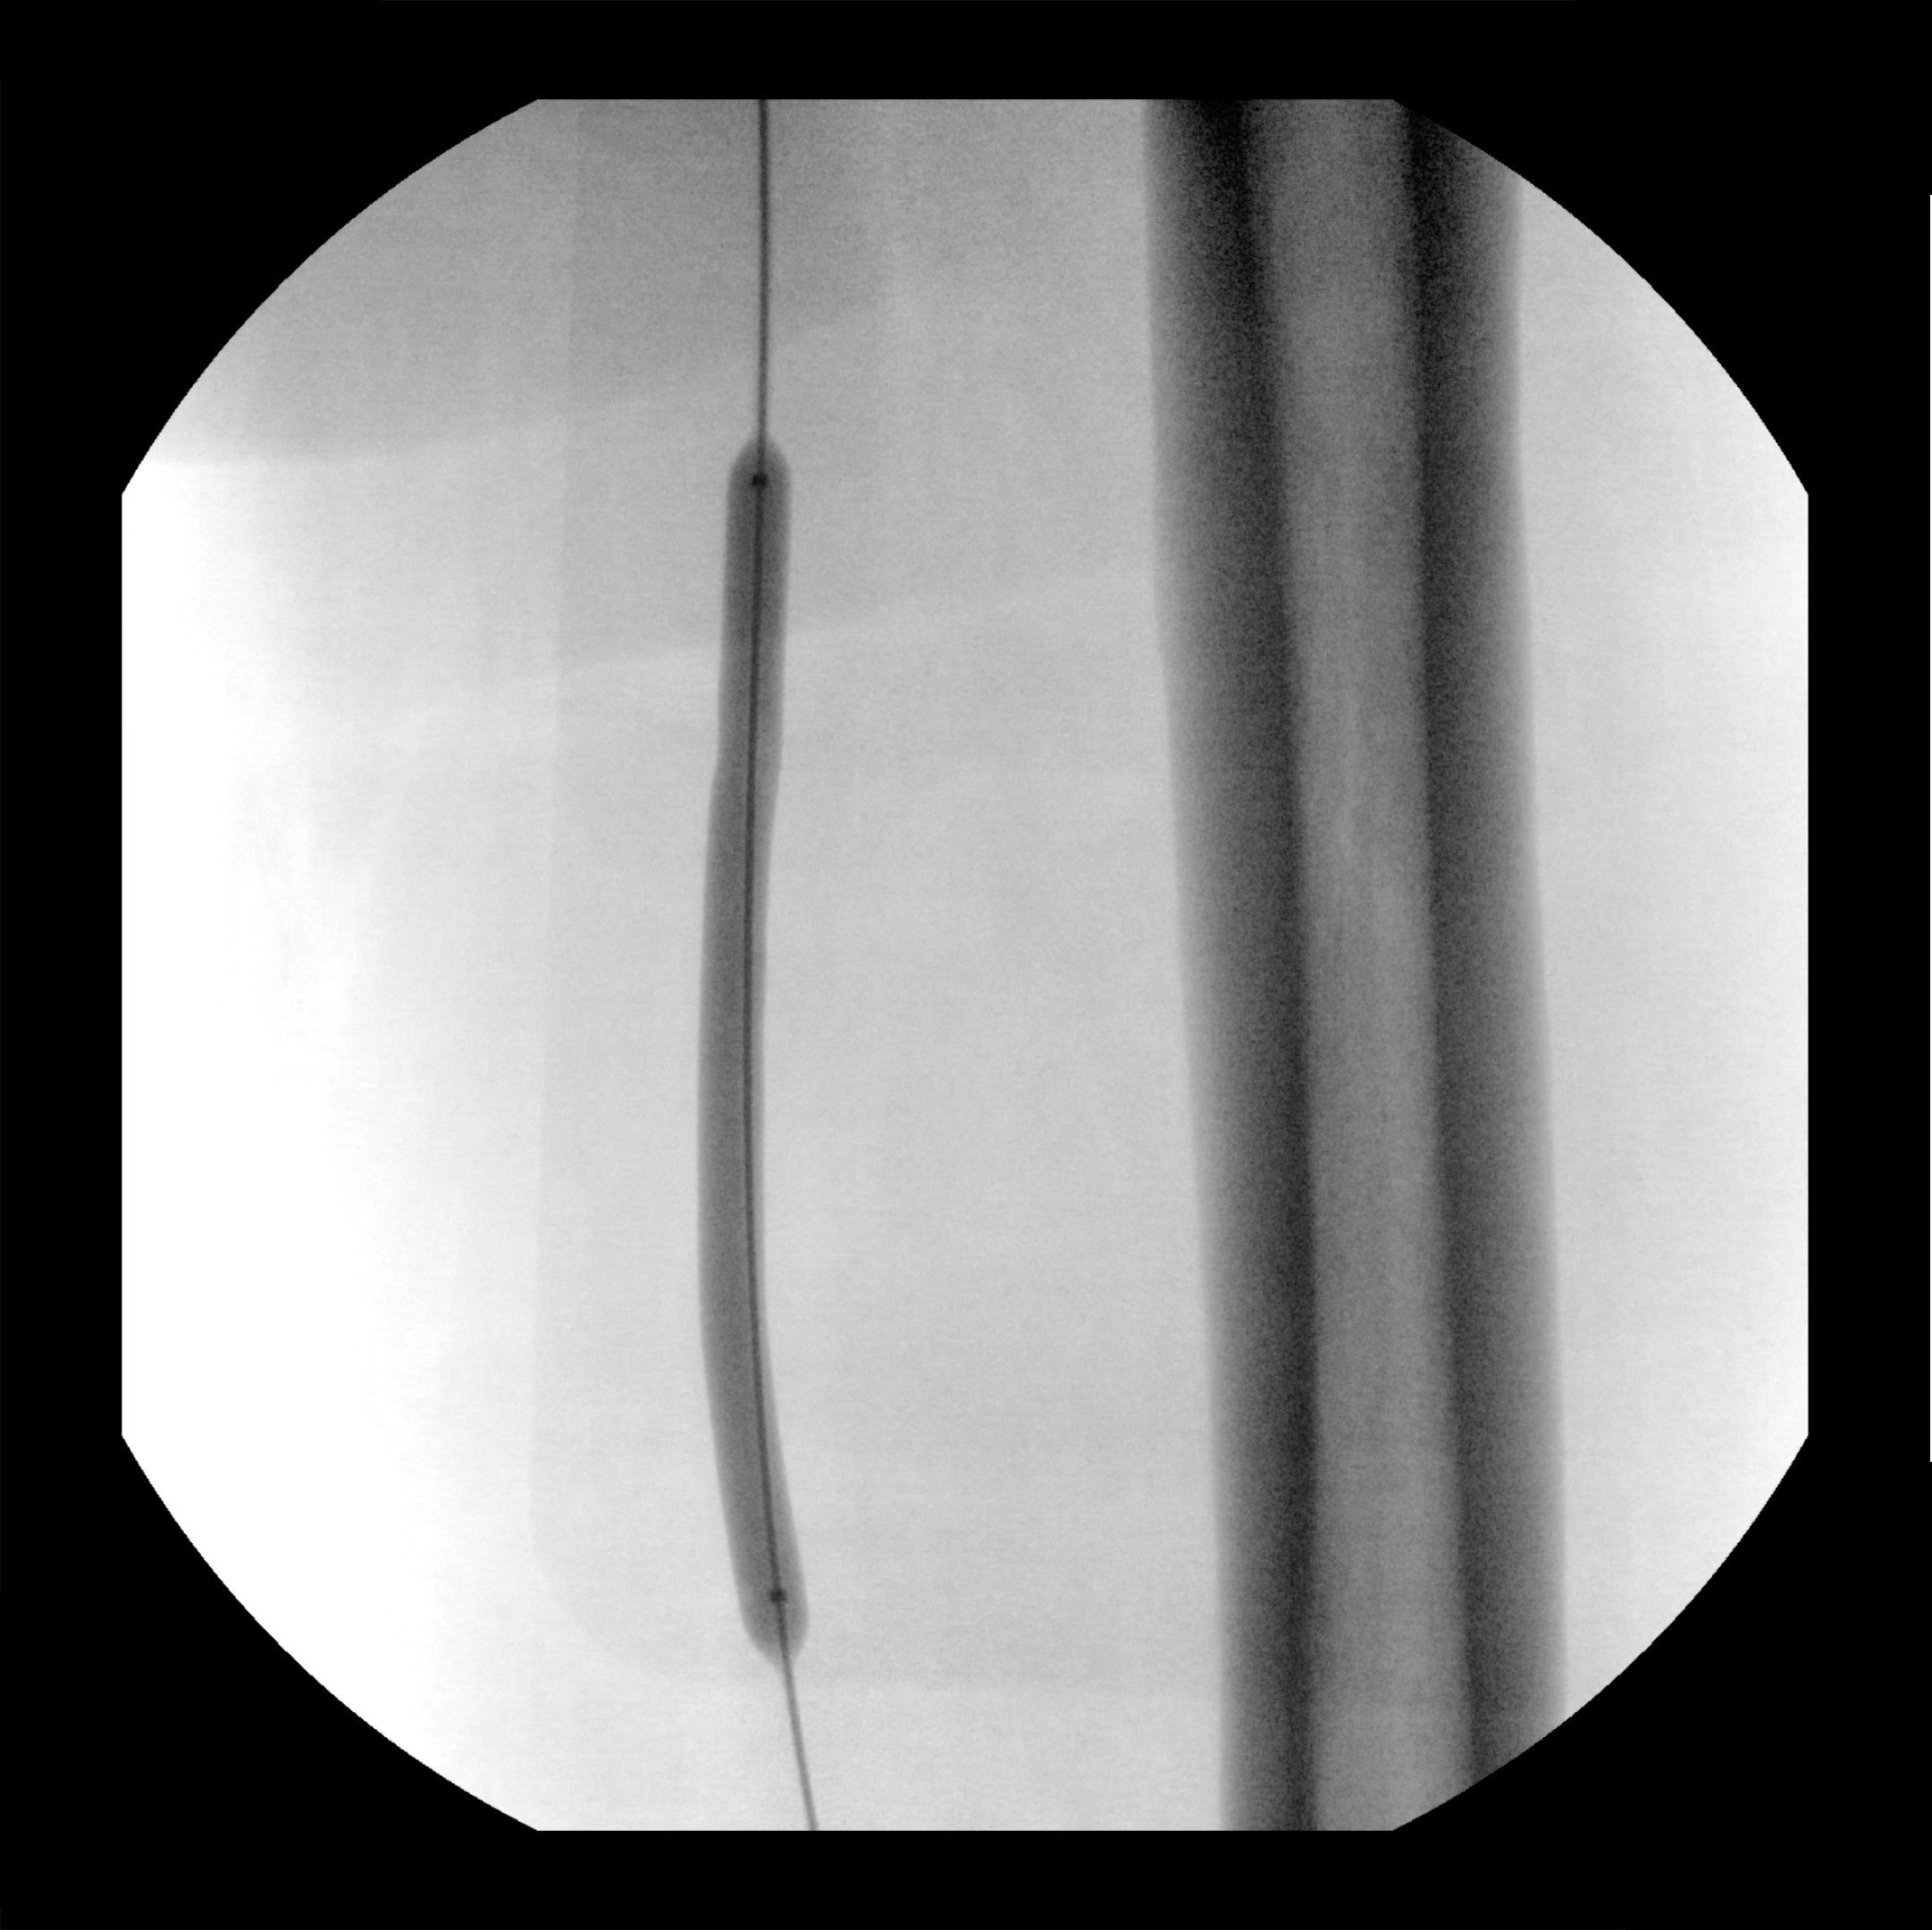

Advanced Features such as Live zoom for dose level optimization

View 4x image size with Live Zoom without increasing the dose (vs Magnification modes) and visualize guidewires

as small as 0.014” in peripheral vascular procedures.

as small as 0.014” in peripheral vascular procedures.